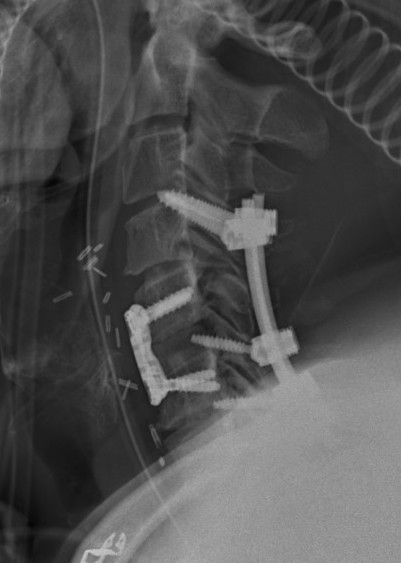

Posterior approach

Advantage

- easier to reduce as direct access to facets

- biomechanically stronger fixation

Technique

- distraction manoeuvre

- instrument between pedicles to reduce

- posterior stabilization or anterior stabilization